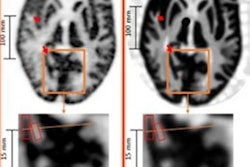

Images of a 59-year-old woman with SCC of the floor of the mouth (star). Both the CT and PET images depicted bilateral, enlarged/hypermetabolic lymph nodes that are suspicious for nodal metastases (arrowheads). However, histopathologic analysis revealed only inflammatory and reactive changes with prominent reactive secondary follicles of the lymph node. There was no evidence of cancer. Hematoxylin-eosin, original magnification ×20 in histopathologic analysis.The accuracy of FDG-PET/CT in localizing primary tumor, lymph node, and distant metastases was tested and compared against histopathologic characteristics of tissue samples. Two experienced, board-certified nuclear medicine physicians with access to relevant clinical data independently rated the whole-body and cervical PET/CT imaging results.